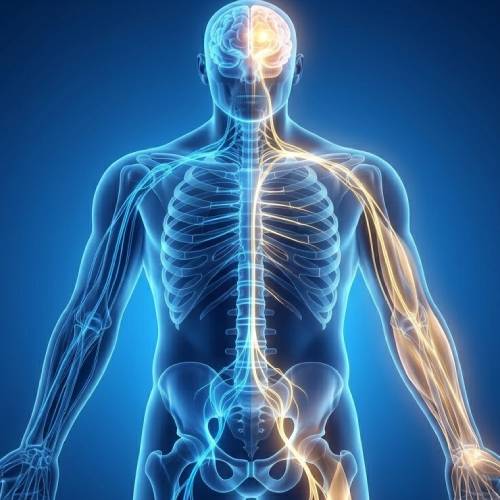

Neurotherapy is a natural, drug-free therapy that works by stimulating specific reflex points and nerve pathways in the body to support healing and improve function.

The therapy is based on the understanding that many health concerns may be linked to nerve imbalances, poor circulation, or blocked energy pathways.

Improve nerve function

Enhances Nerve Function

Directly supports the proper and healthy functioning of nerve pathways.

Supports Internal Balance

Encourages deep harmony and communication between different body systems.